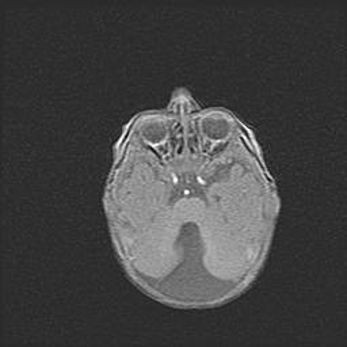

Наружная гидроцефалия с возможной атрофией височных областей.

Возраст: 28 дней

Вес: 3670 г

Пол: мужской

Окружность головы: 38 см

Срок гестации: 40 недель

Гидроцефалия головного мозга у новорожденных – это заболевание, которое характеризуется скоплением избыточного количества спинномозговой жидкости в желудочковой системе головного мозга в результате затруднения её перемещения от места выработки к месту поглощения в кровеносную систему или вследствие нарушения абсорбции. При открытой наружной форме гидроцефалии у новорожденных расширяются и переполняются субарахноидные пространства.

При нормотензивных  формах,  которые,  как  правило,  являются  следствием  перенесенных ишемических  повреждений  паренхимы  мозга,  возможно  сочетание микроцефалии  с нормотензивной гидроцефалией. В основе данных изменений лежит атрофия больших полушарий с преимущественной  локализацией  в  лобно-височных  областях.